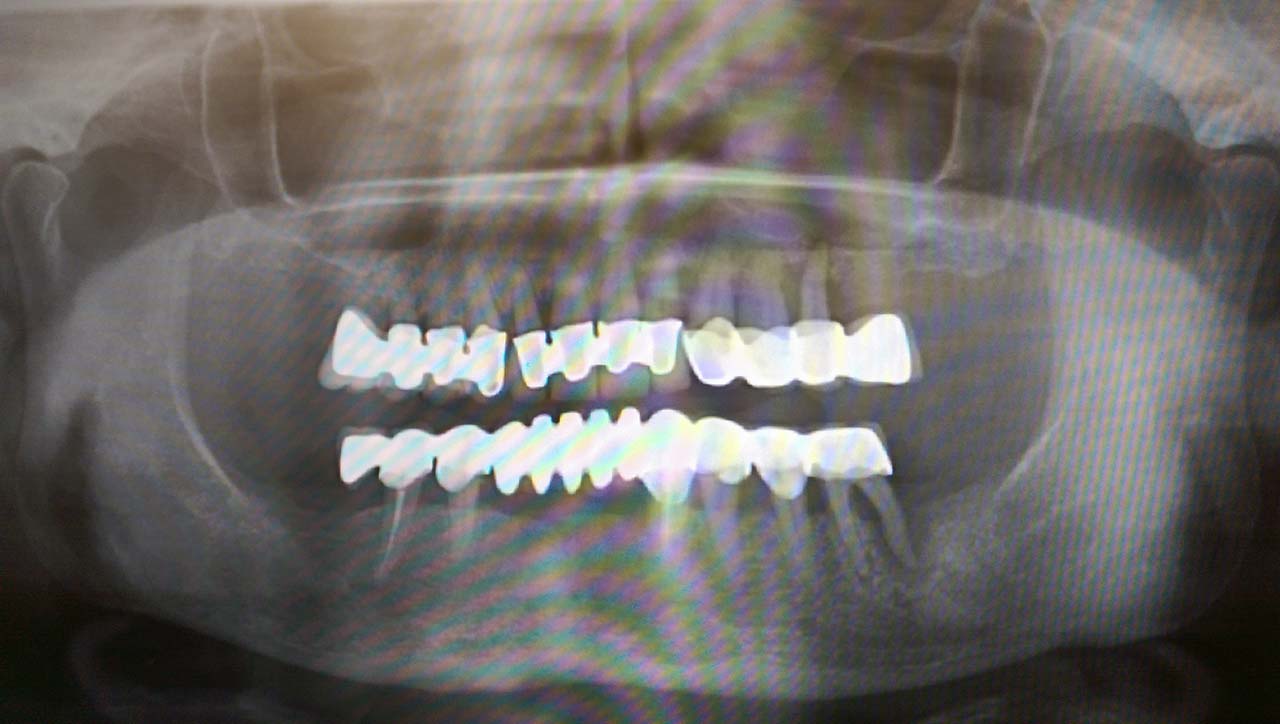

Alsó állcsont teljes rehabilitációja 72 óra alatt, azonnal terhelhető implantátumokkal súlyos paradontitisben szenvedő dohányzó páciens esetében. Az alsó állcsont fogai mind mozogtak az előrehaladott fogágypusztulás miatt.

A fogakat eltávolítottuk, a gyulladt, fertőzött csontot kitakarítottuk, kifertőtlenítettük, majd azonnal implantáltunk.

Svájci, IHDE márkájú, azonnal terhelhető implantátumokat helyzetünk be, és ezekre harmadnapra rögzített, hosszútávú, fémvázas, esztétikus műanyaggal leplezett hidat ragasztottunk be.

Ezt az ideiglenes hidat a sebek gyógyulása miatt használjuk, de tartóssága miatt véglegesként is használható. A legtöbb esetben, ahogy itt is, 6 hónap múlva porcelán hídra cseréljük, a teljes gyógyulás után.